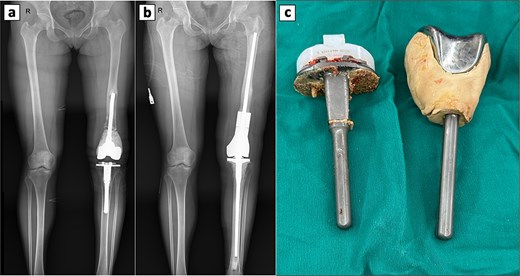

Four years later, persistent knee pain prompted further work-up. X-rays showed radiolucent lines around the tibial component, suggesting loosening, while alignment was intact and osteolysis was absent. A revision TKA was performed through the previous scar using a standard anterior approach. Intraoperatively, the femoral cement mantle was loose and the synovium inflamed and hypertrophic, so the original prosthesis was removed (Fig. 3c). Residual cement was cleared, and the tibial component was extracted. Interface tissue demonstrated a foreign-body granulomatous reaction. A megaprosthesis was implanted, and the procedure was completed without issues (Fig. 3a and b). The postoperative course was uneventful; the patient was discharged on day 12, with pain well controlled at the two-week follow-up.

Perioperative radiographic imaging and retrieved prosthetic components following revision total knee arthroplasty. (a) Anteroposterior radiograph after primary total knee replacement, showing the femoral prosthesis loosening. (b) Anteroposterior radiograph after revision total knee replacement. (c) Retrieved prosthesis from the primary total knee arthroplasty, including femoral and tibial components.